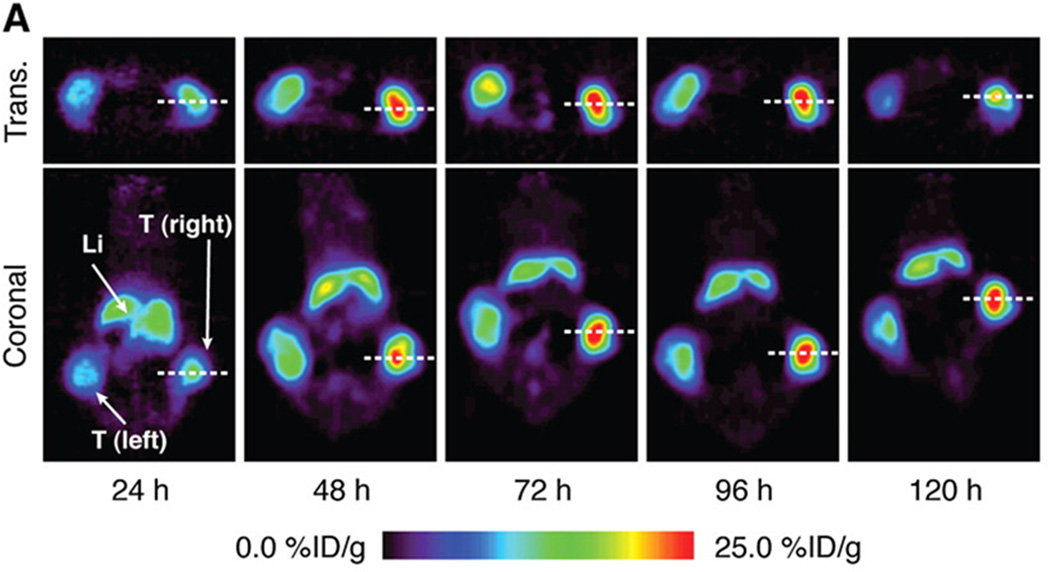

Figure 1.

Axial CT (A), fused FDG PET/CT (B) and fused FDHT PET/CT (C) images demonstrate the biological diversity of bone metastases in patients with castration-resistant prostate cancer. Subtle groundglass and miliary density lesion in T12 vertebral body (arrows), with marked glycolytic activity but minimal androgen expression, as evidenced by uptake on FDG but not on FDHT PET.